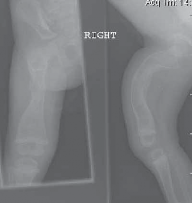

Precision Proximal Femoral Varus Osteotomy Using a 90-Degree Blade Plate

Chapter 27 Proximal Femoral Varus Osteotomy Using a 90-Degree Blade Plate Tom F. Novacheck DEFINITION Proxima…